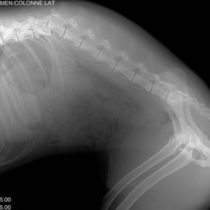

Radiodiagnóstico

En nuestra clínica utilizamos la radiología como método para conocer el estado de tejidos blandos como huesos y articulaciones. Mediante esta técnica poco invasiva, localizamos diferentes daños internos, fracturas, cuerpos extraños, tumores, etc.. de forma rápida y sencilla, facilitando los diagnósticos.